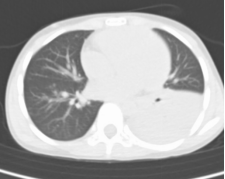

重症肺炎支原体肺炎,可出现呼吸困难、胸痛、咯血等表现。肺部CT可见:塑形性支气管炎、胸腔积液、肺实变和坏死、肺栓塞等表现(如下图)

③影像学表现实变胸腔积液